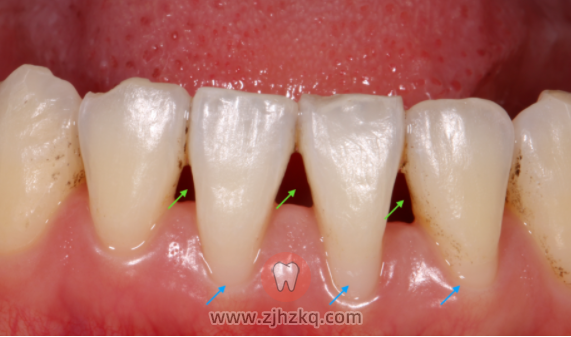

牙龈退缩是指牙龈边缘由牙冠牙根交界处向牙根方向退缩致使牙根暴露。

牙龈退缩带来牙根暴露,冷热刺激下容易出现根面敏感不适,若口腔卫生保持不佳,则可能进一步发展出根面龋坏。两牙间的牙龈乳头退缩,牙间隙增大,出现黑三角,容易出现水平型食物嵌塞。且牙根暴露也会影响美观。